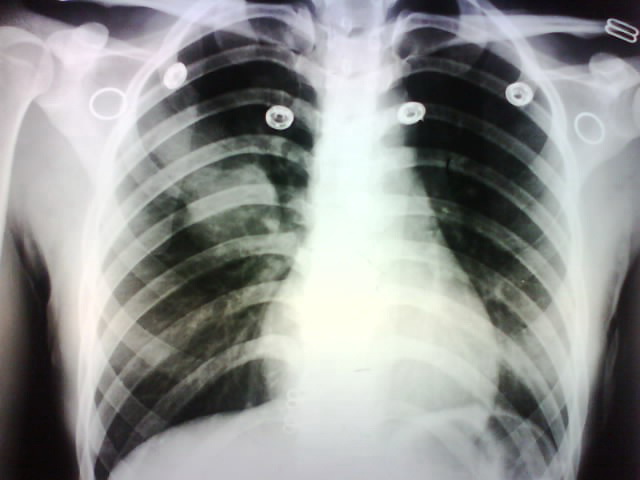

标题: X4932:女,22岁.体检发现.请各位分析可能是什么. [打印本页]

标题: X4932:女,22岁.体检发现.请各位分析可能是什么.

右肺上叶前段病变,临床资料太少,不好定。建议查血象、ct进一步检查。

右肺上叶前段病变,因是体检发现,估计没有临床症状,考虑良性占位,不除外结核。

年轻女性,没症状,结核的可能性较大。

右侧乳腺阴影较对侧淡,显示欠清。作ct或详细询问病史,排除乳腺术后改变。

炎性假瘤或硬化性血管瘤。

考虑右肺上叶良性肿块;建议行进一步检查。

考虑肺内占位性病变 畸态瘤可能

结核?动静脉畸形??进一步检查吧

考虑右肺上叶良性肿块;建议行进一步检查,比较可靠。

左下也好像有问题呀 .考虑结核可能性大.建议进一步检查.

病灶位于上叶前段,不是结核好发部位,不过患者较年轻,又是体检才发现的,考虑结核可能性大,但单就一平片,很难做出最后更有说服力的结论,所以还是建议ct

有难度?!明显的结核,不是我把医影黑掉!